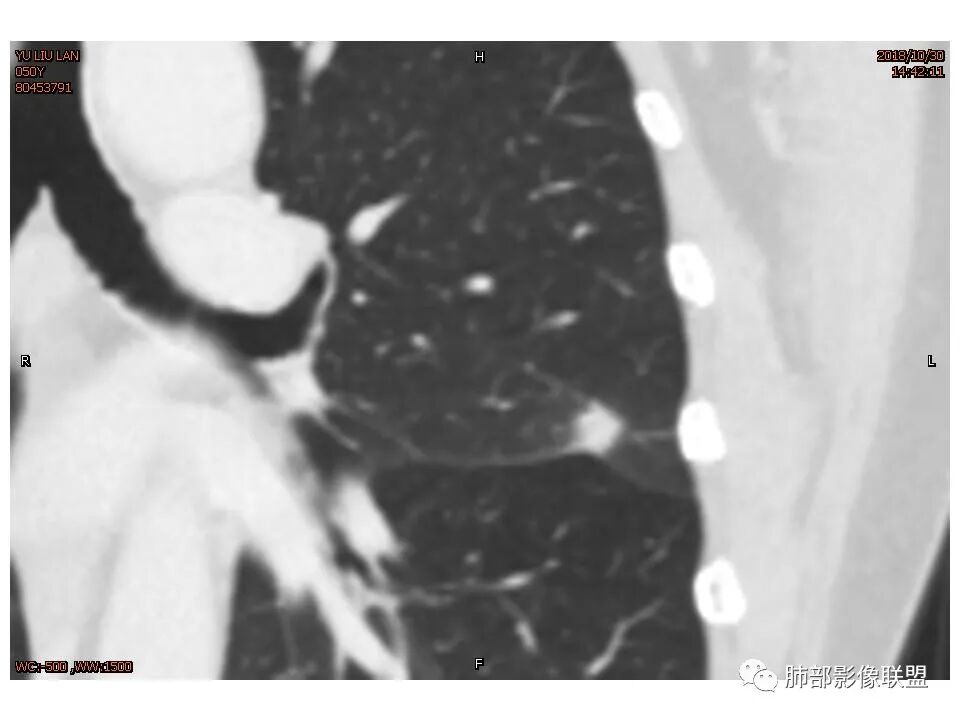

定位左舌,结节,有晕,晕中软毛刺,长毛刺与胸膜牵拉,收缩明显,部分呈方形,明显强化及延迟强化,有支气管近端进入远端阻塞,部分呈鬼脸

鉴别:腺癌 牵拉斜裂,有动静脉相连,

考虑恶性可能性大,毛刺分叶,局部膨隆。收缩明显,牵拉叶间裂

考虑恶性可能性大,毛刺分叶,局部膨隆,牵拉叶间裂收缩明显

因为南大说过实性病变有收缩力往往是慢性炎症。而腺癌毛玻璃才会牵拉叶间裂

有一些地方膨隆,肯定不放心,但是大部分还是平直收缩,要我读片我也炎症放前面,肺癌待排。但是现实生活我会建议切除

轴位像炎性,冠状、矢状位像恶性,真遇到了,纠结

1.胸膜下略不规则实性密度结节影,孤立,缺乏典型深分叶,可见淡薄边界模糊磨玻璃晕,可见相对细长软毛刺。

2.如南边老师分析,病灶缺乏边缘膨隆优势,甚至部分平直内收。